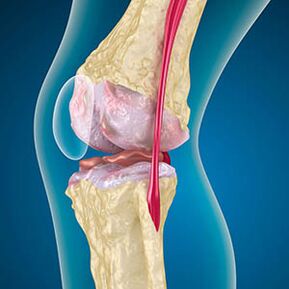

Avec l'arthrose, le cartilage tapissant les bords des os est l'abrasion ou complètement absent. Le tissu endommagé n'est pas une source de douleur, car il n'a pas de récepteurs. L'inflammation dans les structures voisines provoque des symptômes caractéristiques.

Le corps continue la régénération des tissus endommagés, mais le cartilage se développe de manière inégale. En conséquence, des irrégularités se forment qui blessent d'autres éléments de l'articulation. La nature des ostéophytes s'explique par la compensation pour le cartilage articulation lisse. Une autre version indique que la croissance des "éperons" Il est associé à une tentative de stabiliser l'articulation médiale ou latérale en raison d'un affaiblissement musculaire.